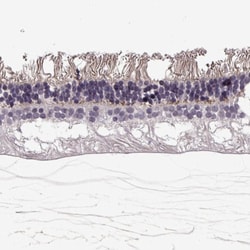

Invitrogen™ TMEM16B Polyclonal Antibody

Calcium-activated chloride channels (CaCC) are present in many cell types and mediate physiological functions such as epithelial secretion, sensory signal transduction, and smooth muscle contraction. Subunits of these CaCC's include the transmembrane proteins TMEM16A and TMEM16B. TMEM16B is predicted to have eight transmembrane domains with both the amino and carboxy termini in the cytoplasm and is expressed in several tissues including olfactory sensory neurons as well as photoreceptors in mammalian retina. Like TMEM16A, TMEM16B is thought to form at least part of CaCC's but has different biophysical characteristics such as voltage dependence and unitary conductance.

| Applications | Immunohistochemistry (Paraffin) |